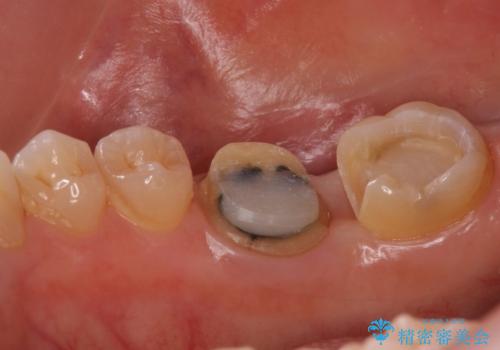

- 右下奥歯の詰め物が取れたとのことで来院されました。

セラミックでの治療をご希望されましたが、残っている歯が少なかったためクラウンでの治療を行いました。

残る歯が薄かったり、十分な量を確保できない場合はクラウンで治療した方が今後の破折リスクを抑えることができます。